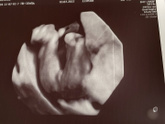

Девочки кто уже не в первый раз может больше опыта имеете , в 17 недель пришла на узи узистка отправила на три буквы мол что пришла ниче тут ещё не видно кто, сегодня 18 недель на узи сказали мальчиком не пахнет а я смотрю и толком понять не могу как … Читать далее